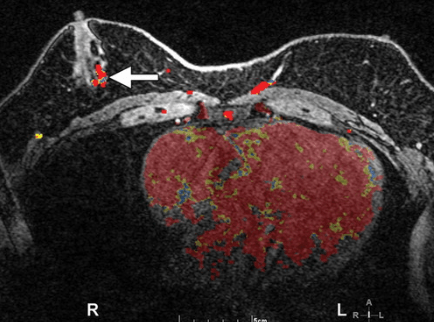

MRI

MRI is also not routinely used in the surveillance of gynecomastia, this case demonstrates the MRI appearance of a nodular bilateral asymmetric gynecomastia. [12]